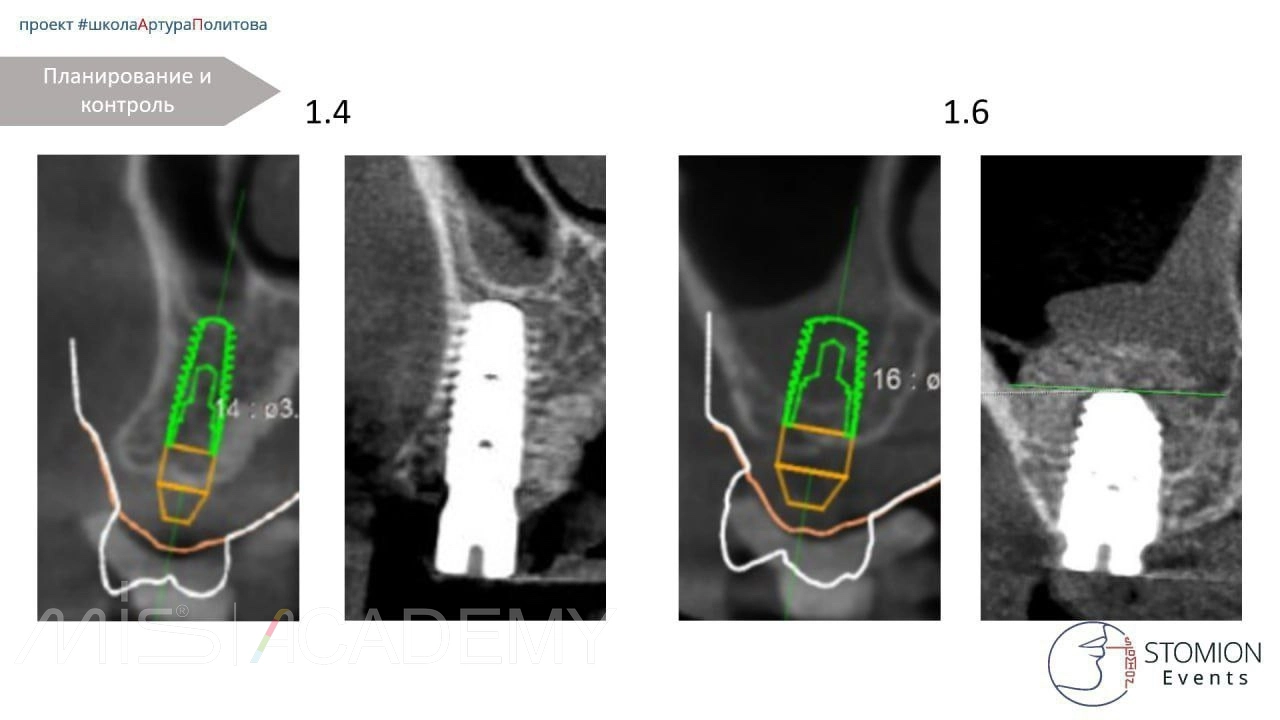

— Проведена имплантация MIS C1 в позициях 1.4, 1.6.

— Особенности операции в области 1.6:

Выполнена операция транскрестального синус-лифтинга (ТКСЛ). Высота нативной кости в области шейки имплантата составляет 2-2,5 мм. Дно гайморовой пазухи приподнято на 8 мм. Уложен остеопластический материал Bio-Oss S. Вариант без костного материала был возможен, однако для данной высоты подъема дна пазухи было принято решение о перестраховке с использованием костного графта.